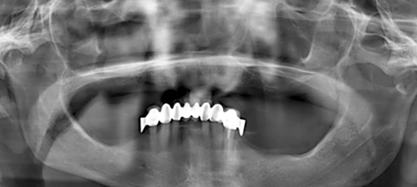

為了最大程度利用現(xiàn)有骨量,需要一個(gè)全程引導(dǎo)式的種植外科手術(shù)導(dǎo)板。在“以修復(fù)為導(dǎo)向”的方案設(shè)計(jì)過程中,根據(jù)CBCT數(shù)據(jù),對(duì)種植體與基臺(tái)中心軸向之間可能的最大夾角進(jìn)行計(jì)算。同時(shí),計(jì)劃拔除 21 牙位之前未發(fā)現(xiàn)的殘根。該牙根之所以至今才檢測到,是因?yàn)榍鏀鄬悠?(OPG) 上呈現(xiàn)出影像重疊(圖 1)。

(圖1)